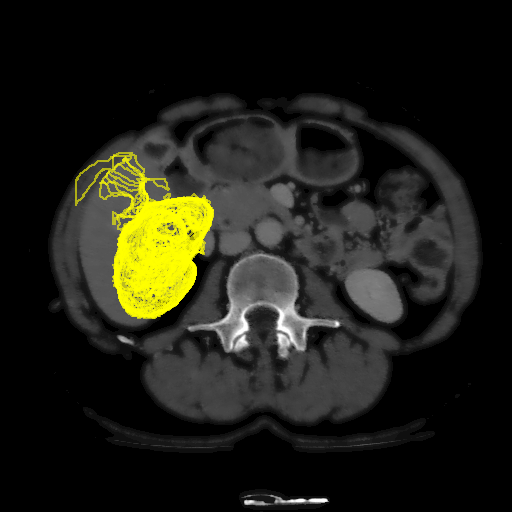

To initialize the tracking process, the organ is segmented in an arbitrary slice of the CT data by a bounding box. The most stable MSHR is then selected in the initialization process for tracking. The respective MSHR is tracked through the slice data along the axis orthogonal to the image data. An example of the tracked regions is visualized for two examples in Fig. 7. Given the segmentations of the single slices, the organ can be reconstructed in 3D. We compare the reconstruction for MSER and MSHR tracking in Fig. 8. To enhance the visualization, the datapoints are triangulated and the surface normals calculated. Since the contrast of the organs can be very low in CT images, the MSER tracking has difficulties catching the organ boundaries. Furthermore, the organ is sometimes partely lighter and darker than the background, which may lead to MSER tracking failure. The proposed MSHR tracking copes well with these difficulties, and the reconstructions are significantly better.

Please note, the tracking of the regions in the CT slices is extremely efficient and only requires an average of 5ms per slice. Hence, for the 45 slices in Fig. 8 the complete 3D reconstruction process, which includes the triangulation (1sabsent1𝑠\approx 1s), the calculation of the surface normals (130msabsent130𝑚𝑠\approx 130ms), and the segmentation (220msabsent220𝑚𝑠\approx 220ms), requires only around 1.5s.

Refer to caption

Figure 8: In the first row, the reconstruction of the liver is displayed for MSER tracking. The low contrast and the fact that the background is partly darker and lighter than the objects makes the reconstruction noisy. The proposed MSHR tracking can cope with these situations and the reconstruction is significantly better.